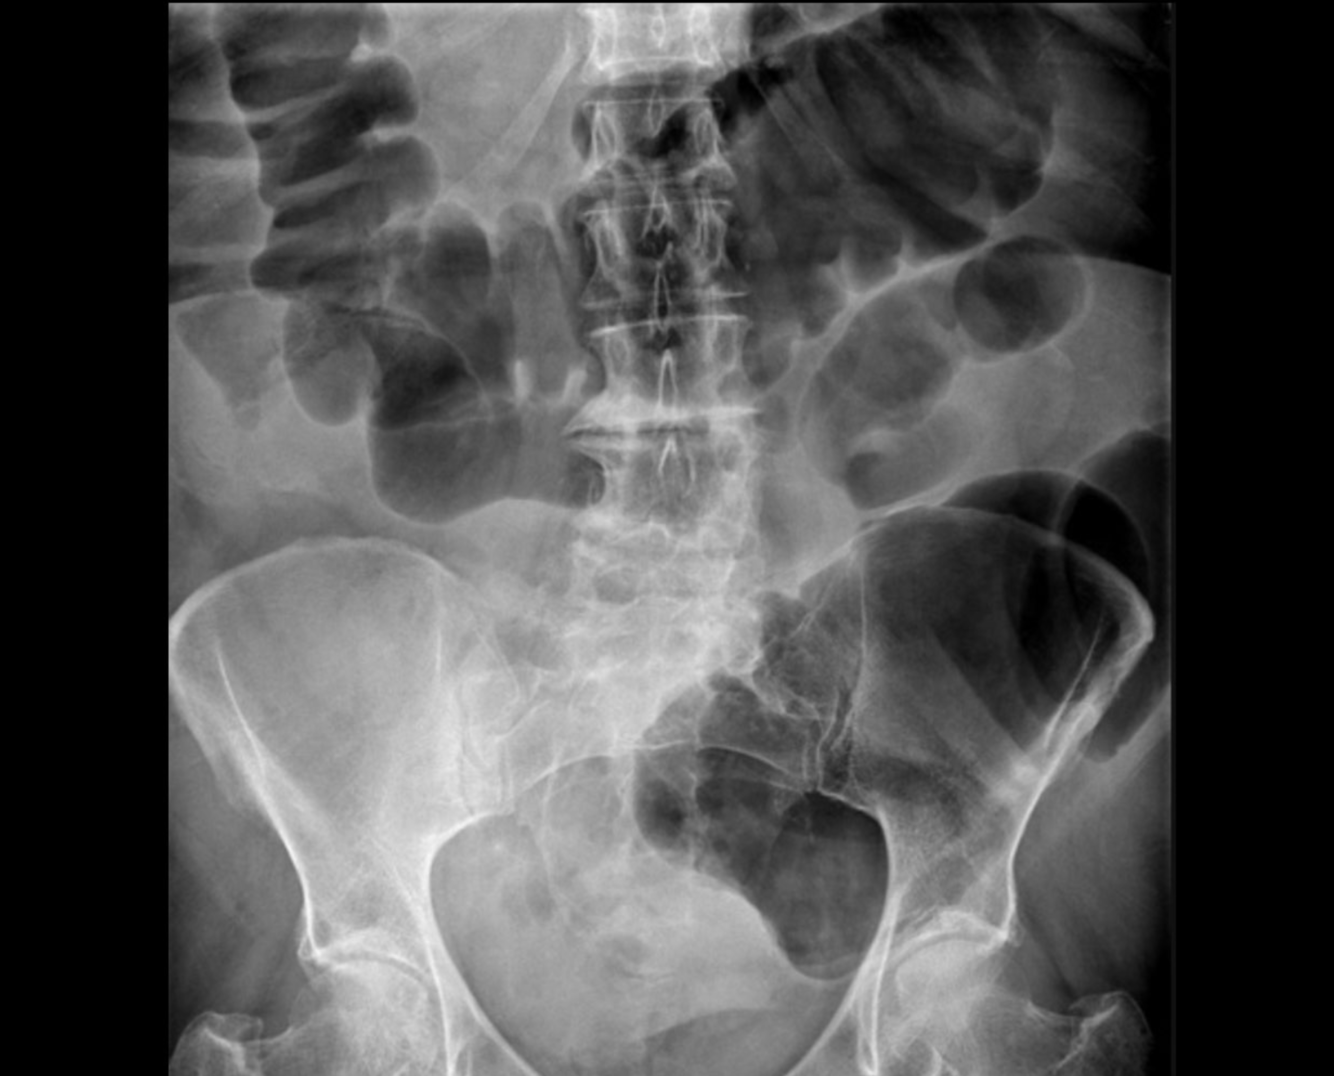

small bowel obstruction

large bowel obstruction

constipation